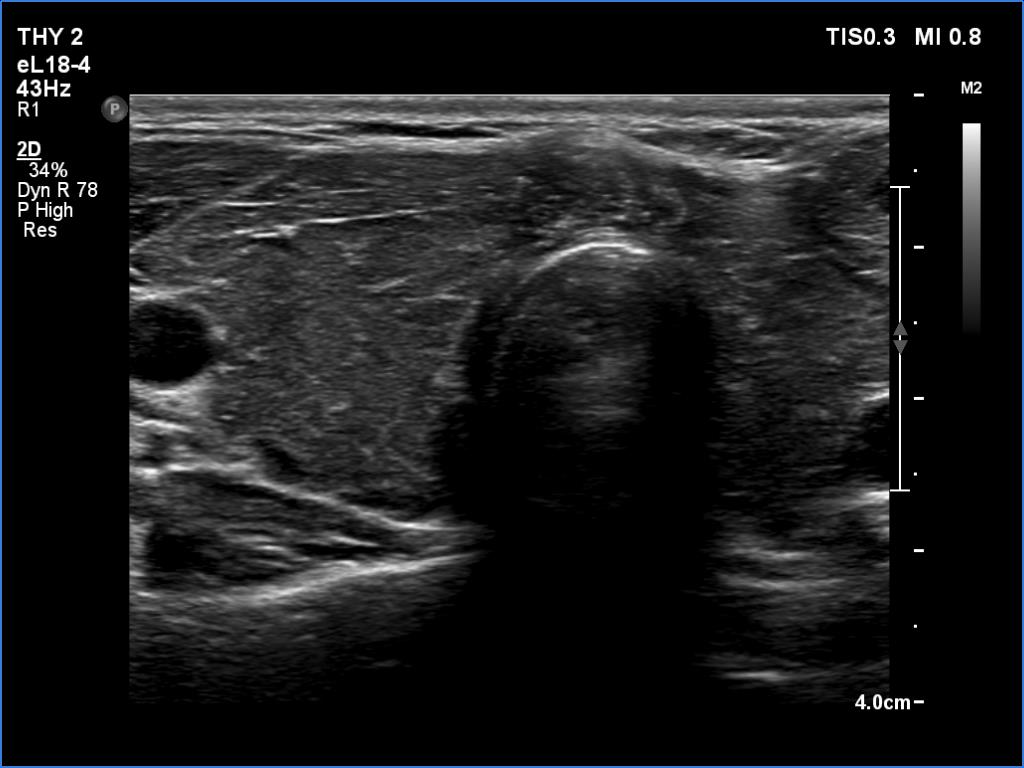

Ultrasonography. The thyroid was moderately hypoechoic and inhomogeneous. There was a deeply hypoechoic lesion in the isthmus which presented microcalcifications. Compared with the extranodular tissue, the nodule was much less vascularized on Doppler and microflow imaging but was harder on elastography.

There were two conditions which favored that the discrete lesion in the isthmus is a true nodule and not a more active focus of the underlying Hashimoto's thyroiditis. Firstly, the palpation which itself was suspicious of a cancer. Second, the presence of microcalcifications. It is worth comparing the similarly deep hypoechoic areas in the left lobe with the presentation of the cancer focus.